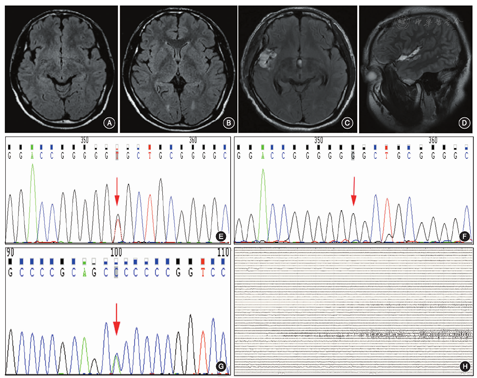

患者男,21岁,主因"发作性幻听伴肢体抽搐6年余"入院。15岁起病,发作表现为双耳鸣(似火车鸣笛低音调)→心悸→意识障碍→咂嘴、吞咽→头眼左偏、口角左歪,左上肢僵硬,持续10 s后缓解,继发强直-阵挛性发作的概率为20%。既往服用卡马西平、左乙拉西坦、丙戊酸、奥卡西平等多种药物,仍控制不佳。其母亲13岁首次出现癫痫发作,数月发作1次,表现为全身强直-阵挛性发作,先兆同患者,25岁分娩,30岁后服用卡马西平,至今无发作。家族其他成员均无癫痫发作史(图1)。近期,1~2个月发作1次。查体:神志清楚、情绪稳定、高级智能活动正常,脑神经(-),四肢肌力、肌张力正常,腱反射存在,病理征(-)。头颅MRI检查显示,右侧颞极、颞叶内侧、岛叶、前环岛沟、颞盖皮质均可见信号增高,增强无强化(图2A,图2B)。头颅正电子发射断层显像术(PET)-CT检查显示,右侧大脑半球的额叶、颞叶、岛叶及顶叶表现为低代谢。视频脑电图显示发作间歇期背景活动无异常,可见癫痫样放电,清醒期主要位于颞叶,睡眠期较泛化,右半球(额、颞叶区)均可见。韦氏量表评分结果:全量表、言语量表、操作量表、记忆量表分别为105分、109分、98分、112分。术前头皮脑电图检查显示,发作起始于右侧半球,考虑致痫区为右侧颞叶,右侧听觉皮质起始的可能性大。全外显子基因检测(迈基诺基因公司)的结果显示,RELN和NOTCH3突变,均来源其母(图2E,图2F,图2G)。术前根据辅助检查结果综合考虑致痫区为颞横回,需在颞叶内侧、颞极、额眶区植入电极进行鉴别,同时在顶下小叶植入电极确定手术切除后界,故以颞横回为中心进行电极植入术,以鉴别致痫网络。颅内电极脑电图证实发作起始为颞横回,致痫网络为:颞横回→岛后小叶→海马→扩散颞盖、顶盖(图2H)。患者在全身麻醉下行颞横回、颞盖及右侧岛后小叶切除术。术后病理学检查结果为局灶性皮质发育不良Ⅱa,基因检测结果显示为RELN杂合突变。术后1年随访,患者无发作,复查头颅MRI显示颞横回、颞盖、右侧岛后小叶已切除(图2C,图2D)。